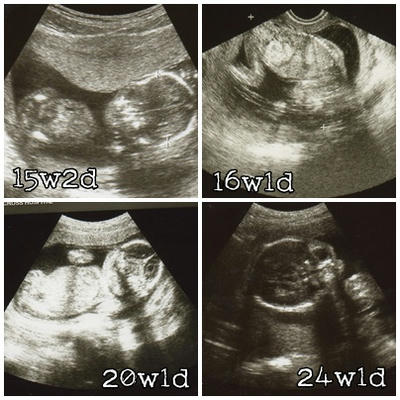

2009/10/27(妊娠4ヶ月 15w2d) 妊婦健診 前期2回目

2009/11/02(妊娠5ヶ月 16w1d) 出産予定病院分娩予約

2009/11/30(妊娠6ヶ月 20w1d) 妊婦健診 中期1回目

2009/12/28(妊娠7ヶ月 24w1d) 妊婦健診 中期2回目

100405_2.jpg